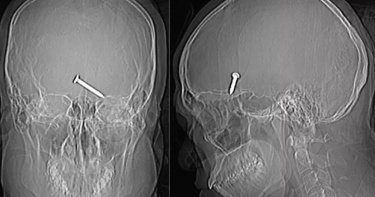

為檢查故障釘槍…他誤將3.2公分釘子射向左眼「插入大腦」 意識清醒僅失明

馬來西亞一名30歲的男子,因不小心將釘槍射向自己的臉,導致左眼開始流血,緊急送往醫院的途中,他的意識相當清醒,且不斷抱怨著「頭好痛」,而醫生在觀察電腦斷層掃描時,發現這支長達3.2公分的釘子已經插進了大腦額葉中。幸運的是,在將釘子拔出後,男子僅僅失去了左眼視力,並沒有造成其他神經功能損傷。根據外媒《UNILAD》報導,這起事件被記錄在《Cureus》(醫學科學雜誌)的一篇醫療報告中,於事故發生當時,一名30歲的男性建築工人正在建築工地上班,而當釘槍卡住時,他準備透過槍管檢查狀況,卻不幸啟動了釘槍,導致他的左眼被釘子射中。報導指出,該名男子是在沒有配戴護目鏡的情況下使用釘槍,才會導致釘子直接射進臉部,而當男子被送往醫院時,由於傷勢相當嚴重,許多人認為他可能活不到隔天,但在醫生的搶救之下,男子於手術後一周就順利出院,除了左眼傷口和腫脹外,並沒有造成其他損傷,狀況恢復良好。據當時的電腦斷層掃描顯示,一支3.2公分的釘子穿過男子的左眼,卡進了大腦額葉中,而男子在整個檢查過程中,精神狀態相當良好、意識清醒,還有精力抱怨「頭好痛」、「左眼好痛」,四肢的肌肉活動也十分正常。 後來,醫生立即為他注射了破傷風、抗生素及抗癲癇的藥物,而在成功將釘子拔出後,男子並沒有繼續出血,除了造成他的左眼視力喪失、無法正常閉眼外,釘子並沒有傷到重要的動脈和神經系統。